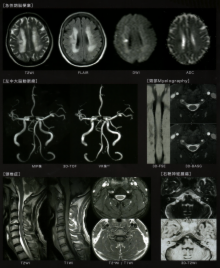

<MRI>

頭部 T1画像、T2画像

FLAIR画像

Dw画像、ADC画像

T2*画像

脂肪抑制画像

MRA画像(3D画像)

造影MRI

脊椎 T1画像、T2画像

ミエログラフィー